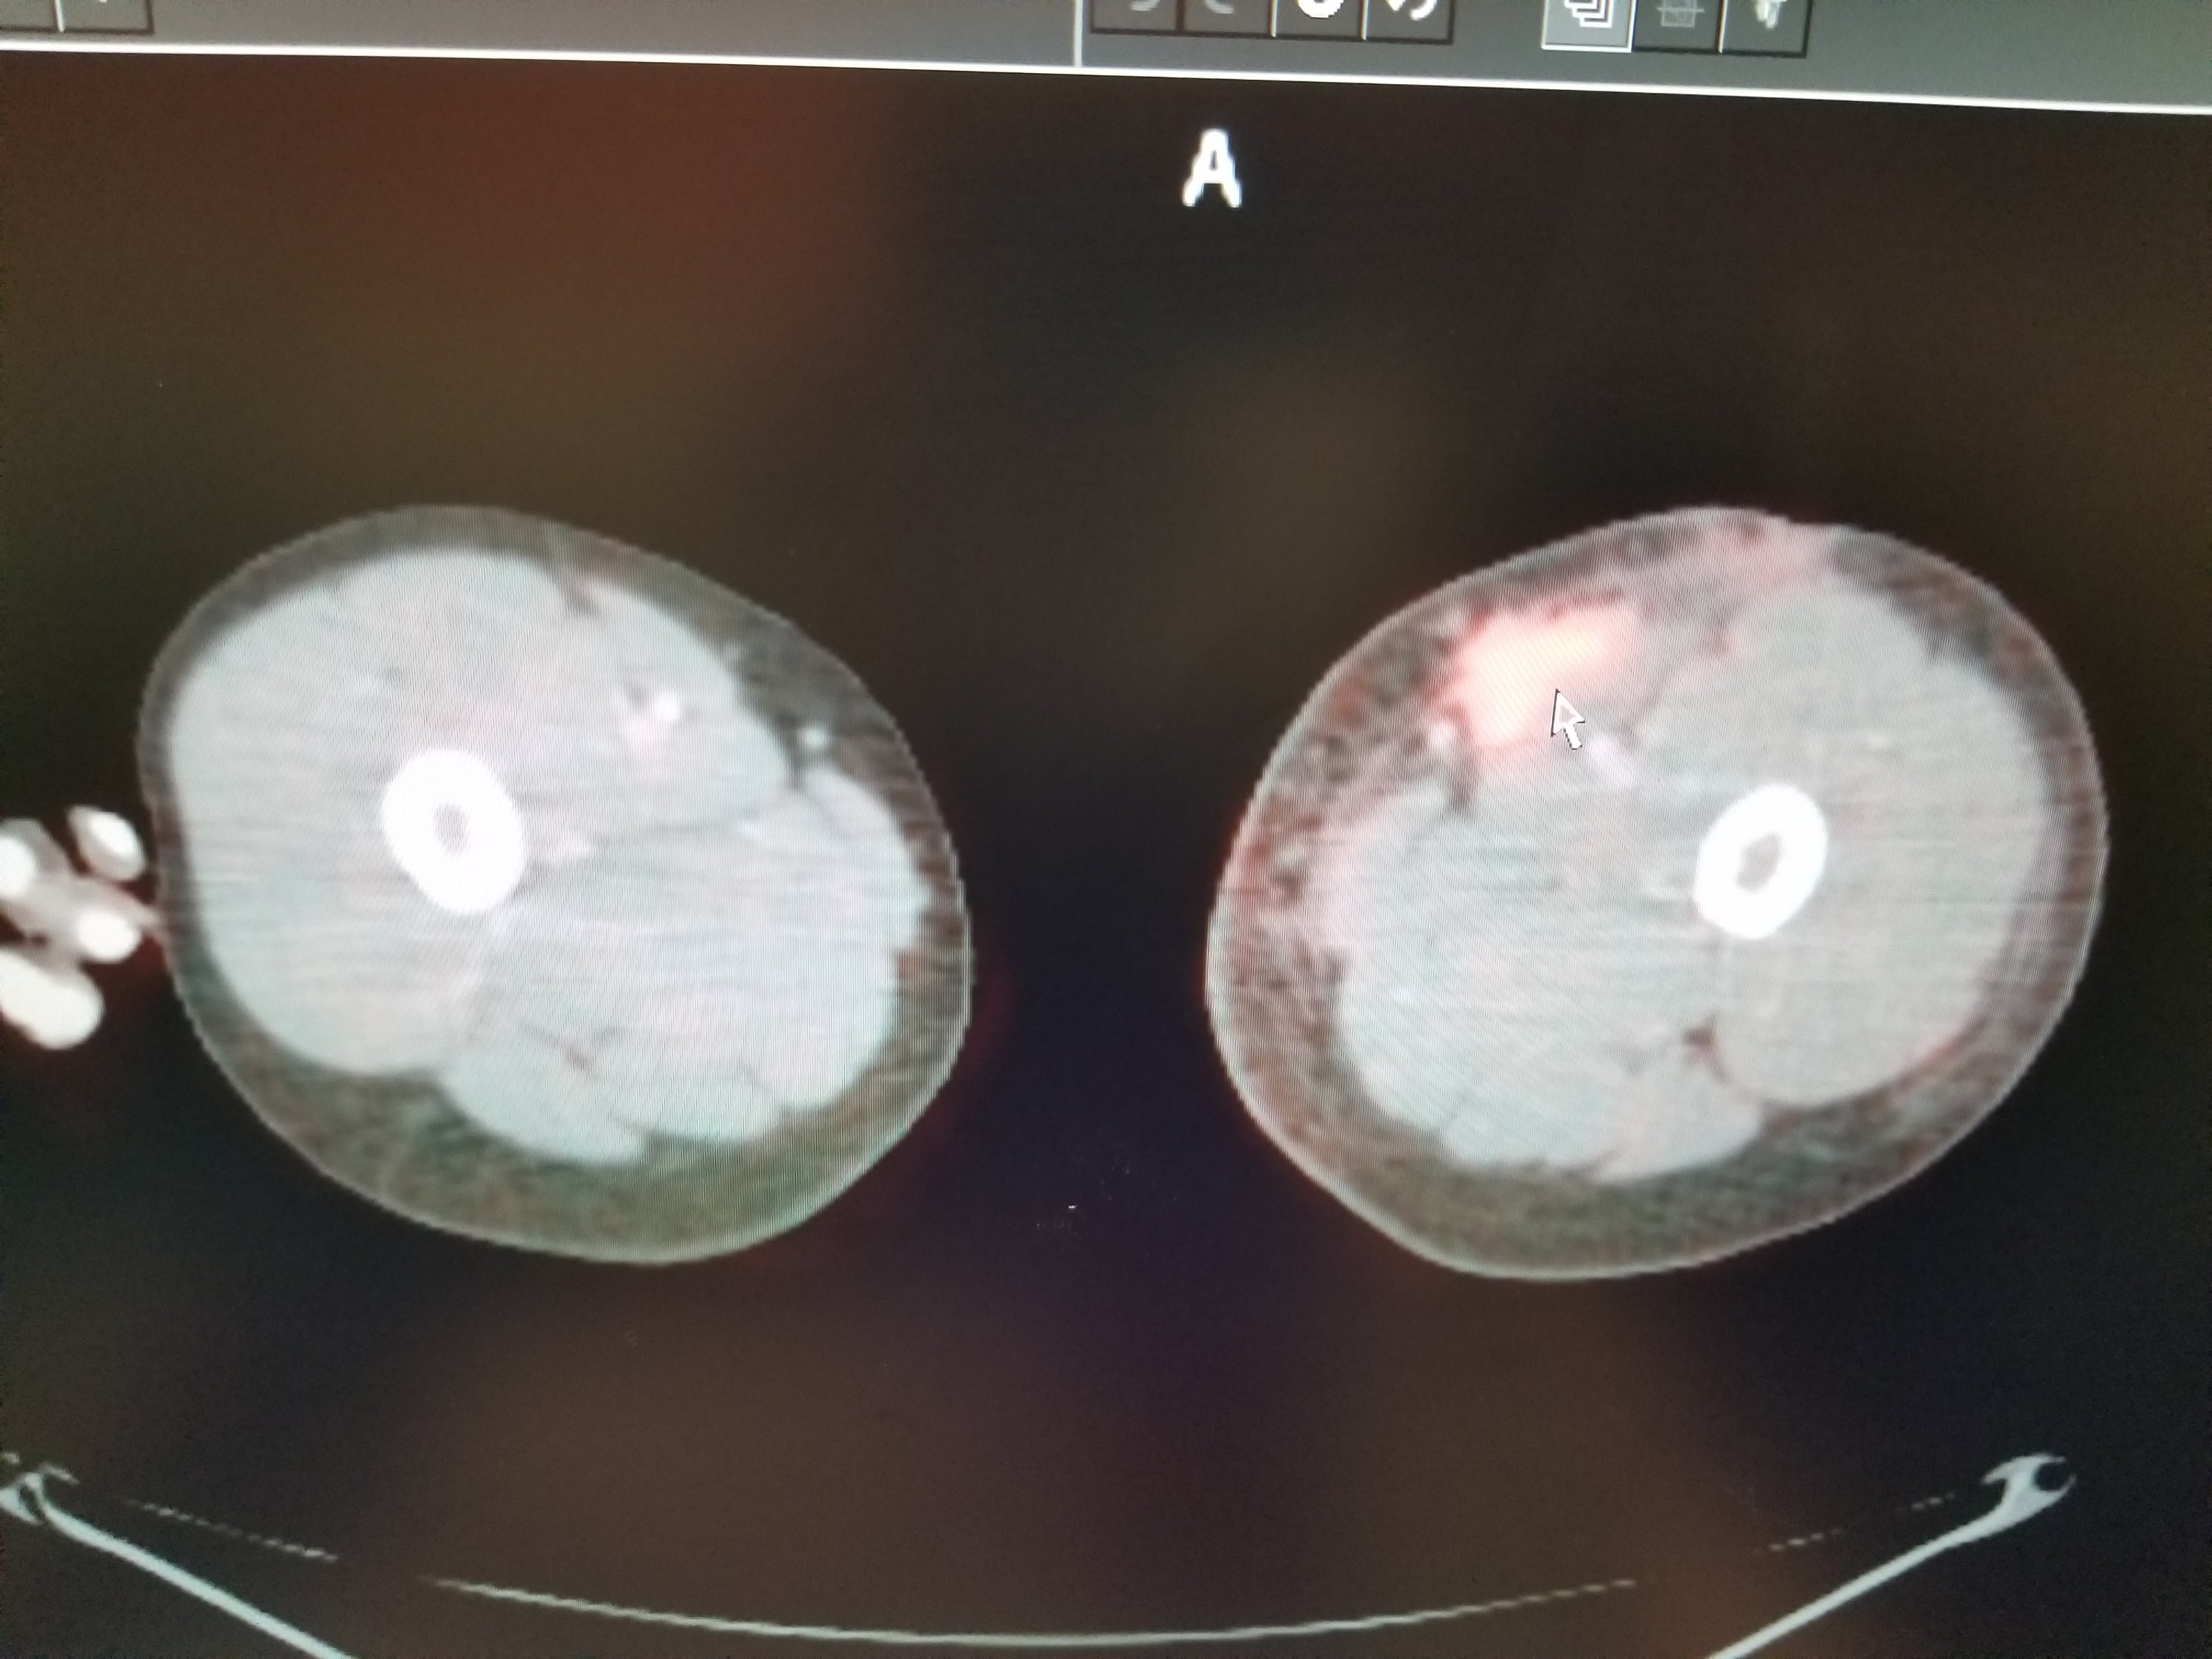

We made great use of the visit by getting him to pull up the PET/CT images so we could check them out. Since we wouldn’t receive the radiologist’s report until Wednesday afternoon, Eli decided to write his own report. Who needs a medical degree for that anyway?

Eli’s report is transcribed below, with the corresponding images (Cancer cells “light up” on the images, but so do some normal things, like the heart, bladder, and brain. They look for asymmetries and things lighting up where they shouldn’t).